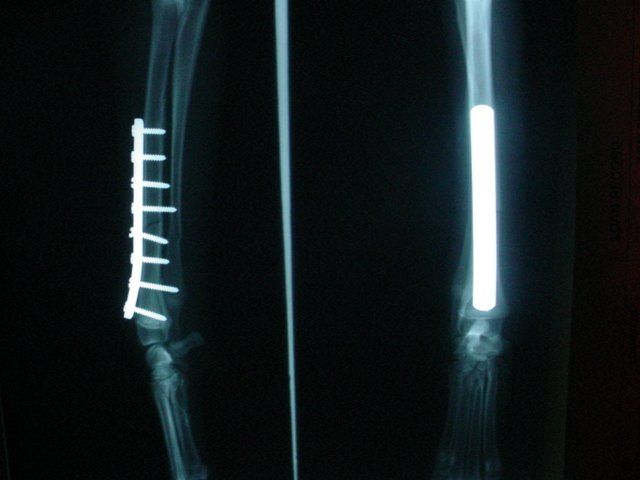

Dogs and cats commonly experience fractures secondary to trauma. The most common cause of the trauma is being hit by a car. Other trauma such as falls from furniture, jumping on unstable surfaces, leaping from a person's arms, etc. can also result in fractures. Below are some x-rays of some of the fractures we have seen at All Pets and their surgical correction using pins, plates, screws, and/or wires.